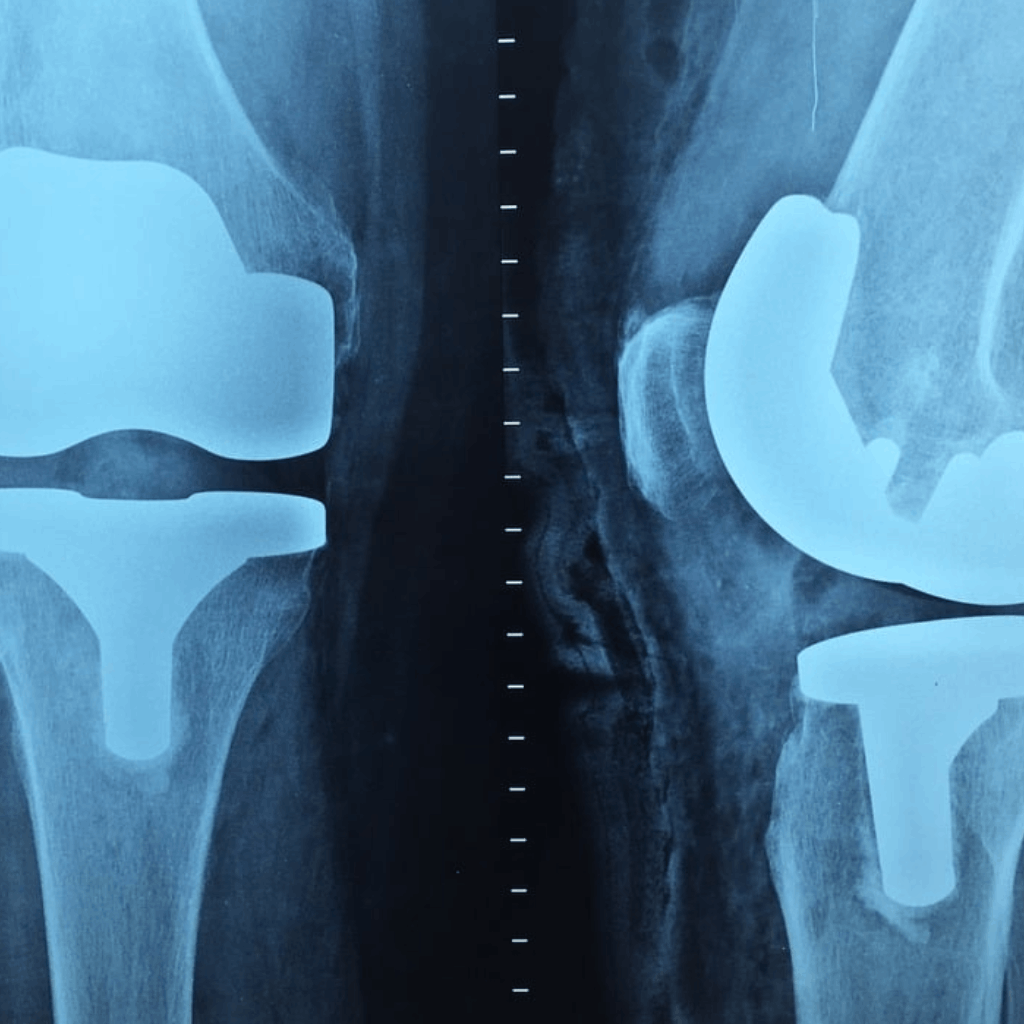

Ortopedia e Traumatologia sono le branche della medicina dedicate alla diagnosi, al trattamento e alla prevenzione delle patologie e dei traumi a carico dell’apparato muscolo-scheletrico.

Si occupano quindi di ossa, articolazioni, muscoli, tendini e legamenti. Nei Poliambulatori aDòc Healthcare, i nostri specialisti offrono un approccio completo e personalizzato per restituirti mobilità e benessere, utilizzando le tecniche più aggiornate per la gestione di ogni problematica ortopedica.